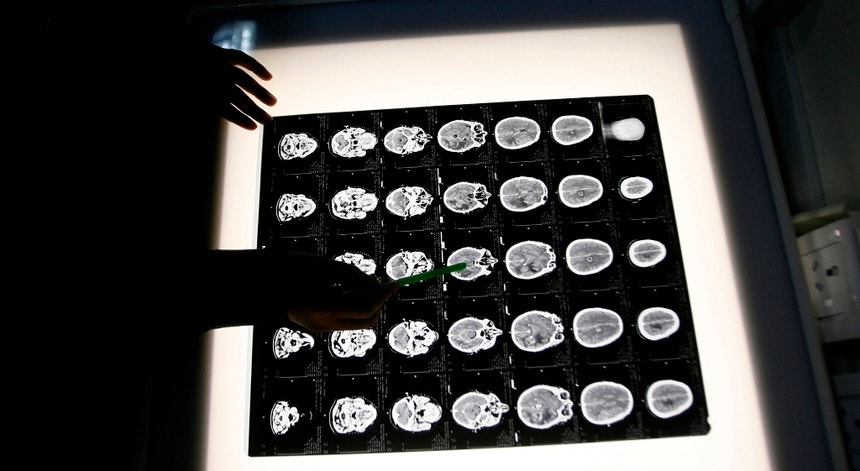

Foto: Reuters